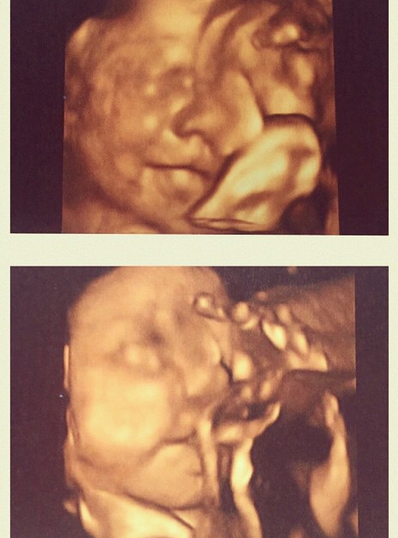

Después de eso, la reportera ha continuado compartiendo selfies que revelan el avance de su gestación. Hasta que la mañana del miércoles, Cristina quiso mostrar la que podría ser la última ecografía 3D de su niña y de paso, confirmar el que será su nombre:

“Mi pequeña Alessandra sonriendo para la foto. Luego prefirió chuparse el dedo”, escribió en Instagram, agregando las etiquetas “amor de mi vida”, “último mes”, “bebé a bordo” y “que llegue julio ya”.